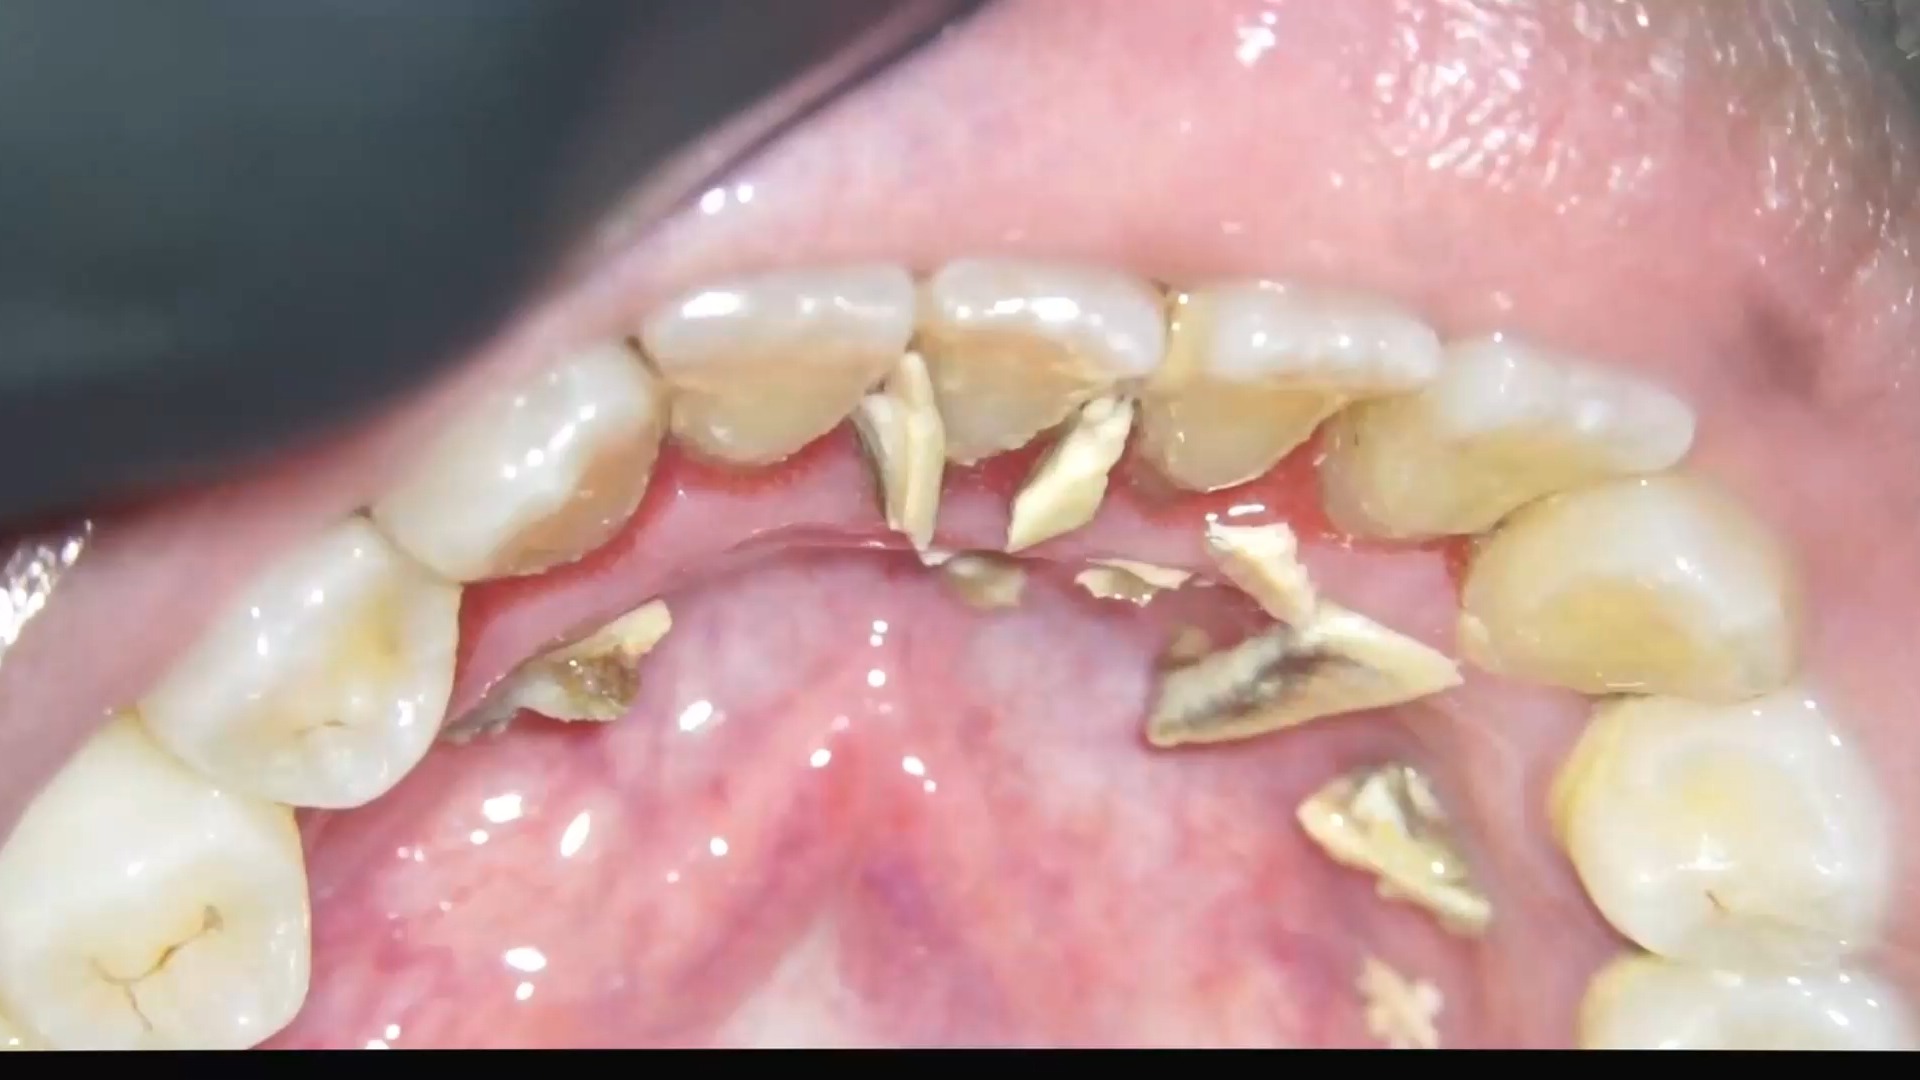

1.肉眼可见的坚硬黄色或棕色沉积物

2.牙龈持续出血、红肿

3.牙结石已延伸至牙龈下方